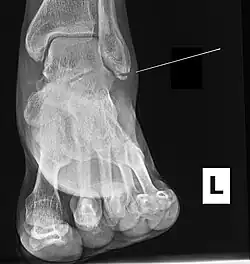

Ankle radiographs are used to detect widening of the tibiofibular syndesmosis or medial clear space. The medial clear space is the area between the talus of the ankle and the medial malleolus. Damage to the deltoid ligament and syndesmotic ligaments result in mortise instability, causing the talus to laterally shift and widen the medial clear space.[4][12] A clinical study, conducted in 2006 and published in the Journal of Bone and Joint Surgery, found that the medial clear space size of a normal ankle and an injured ankle measured at 4 millimetres and 5.4 millimetres in length respectively.[11] To confirm diagnosis, full-leg radiographs are used to inspect for fractures of the proximal fibula and widening of the interosseous clear space (or tibiofibular clear space). The interosseous clear space is the area between the medial side of the fibula and lateral side of the tibia. A peer-reviewed study, published in Injury in 2004, found that an interosseous clear space greater than 10 millimetres indicates diastasis of the syndesmotic ligaments.[4]

If necessary, computed tomography (CT) or magnetic resonance imaging (MRI) may also be used to clarify diagnosis. MRI scans can check for interosseous membrane or tibial tubercle damage if high instability of the ankle is diagnosed.[8][11] Arthroscopy may be used to diagnose a syndesmotic lesion but is often not recommended due to operative difficulty.[13] Stress radiographs of the ankle are used to assess the integrity of the deltoid ligament and tibiofibular syndesmosis.[9][13] The size of the medial clear space can also be measured using stress radiography.[11]

X-ray, CT, or MRI scans can be used to diagnose the extent of the Maisonneuve fracture's damage and determine whether it is a simple or comminution fracture.[8] During diagnosis, a supination-external rotation pattern of injury may also be concluded if there is an isolated fracture of the posterior tubercle of the tibia.[9]